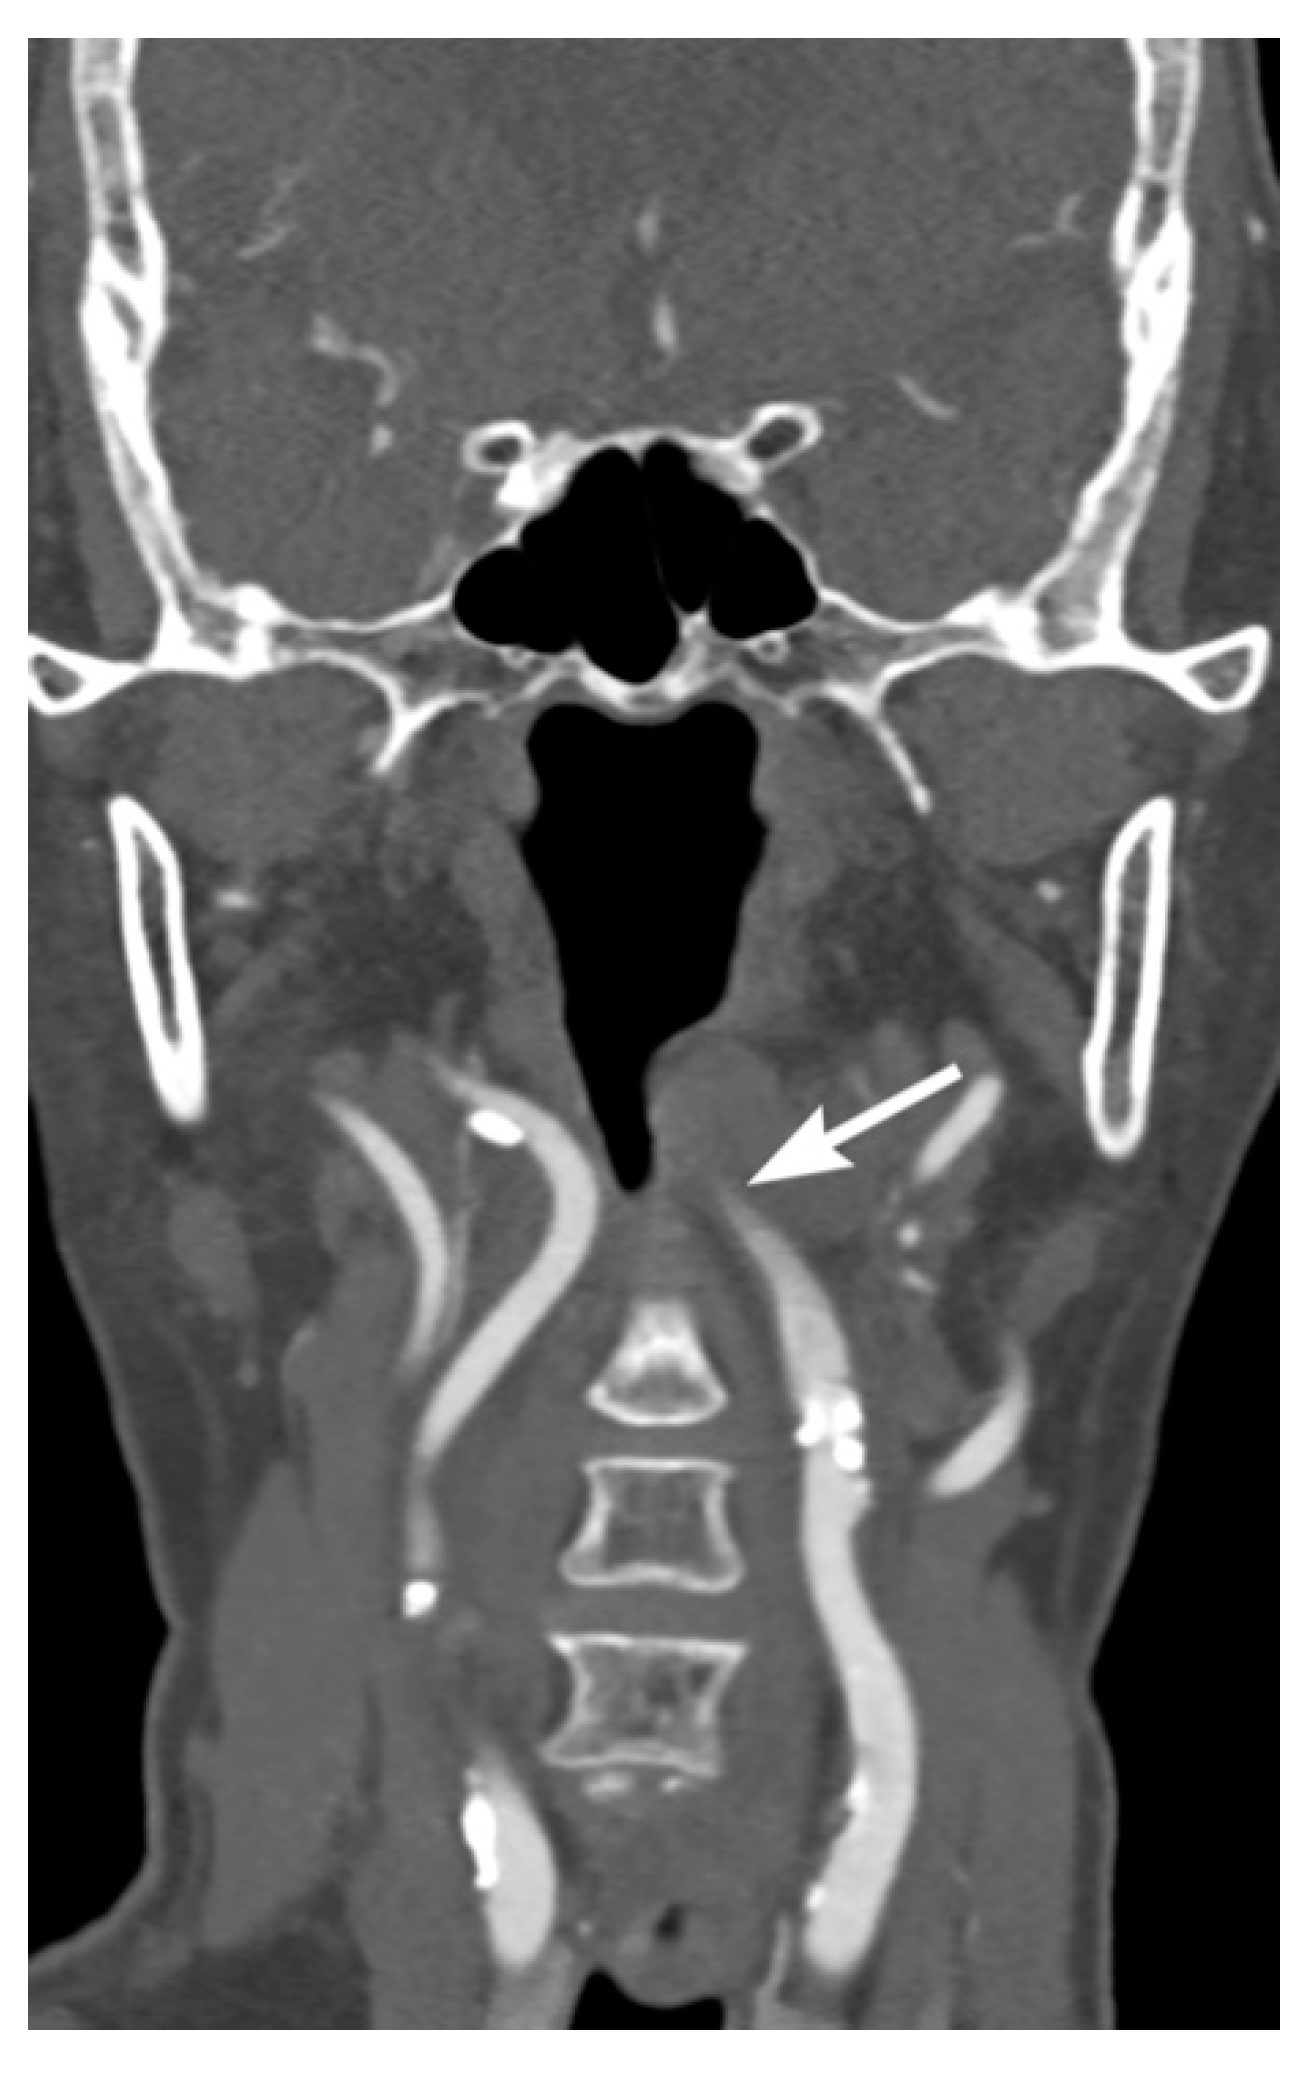

2. Imaging Techniques

3. Imaging Findings of Arterial Injury